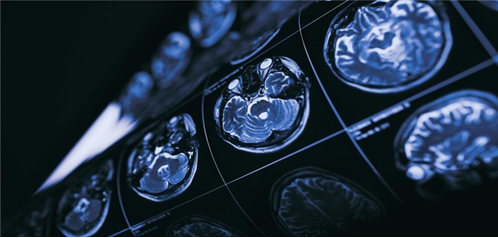

失重状态人体会如何变化?

在太空旅行的早期,科学家们努力研究如何克服重力,使火箭能够不受地球引力的影响而把人类送上月球。如今,重力仍然是科学议程的重中之重,但这次我们更感兴趣的是重力的减弱如何影响宇航员的健康,尤其是他们的大脑。毕竟,我们已经进化到在地球引力(1倍重力)下生存,而不是在太空失重(零重力)或火星微重力(0.3倍重力)条件下生存。

那么,人类大脑究竟是如何应对微重力影响的呢?糟糕的是,大脑被保护在“坚果壳”中,关于这方面的信息非常有限。不过我们知道,宇航员在失重时的脸会变得红肿,这种现象被亲切地称为“查理-布朗效应”(Charlie Brown effect),或者“肿头鸟腿综合症”。这是因为,大部分由血液(细胞和血浆)和脑脊液组成的液体向头部移动,导致他们脸部变得圆胖,腿部则变得纤瘦。

这些液体流动也与太空运动病、头痛和恶心有关。最近,由于血流增加,大脑在颅内向上漂浮,导致血压升高,视力模糊也与此有关,这种情况被称为视力障碍和颅内压综合征。尽管美国宇航局认为这种综合症是任何火星任务的首要健康风险,但要弄清楚导致这种症状的原因,以及如何预防它,仍然是个谜。

对此,南威尔士大学生理学和生物化学教授达米安·贝利(Damian Bailey)认为,大脑的某些部分最终接受了太多的血液,因为一氧化氮(通常漂浮在血流中但却看不见的分子)在血液中积聚。这使供应大脑血液的动脉放松,从而使它们过度扩张。由于血流量激增,血脑屏障(大脑的“减震器”)可能会不堪重负。这使得水慢慢积聚(即出现所谓的水肿),导致大脑肿胀和压力增加,这也可能由于排水能力受限而变得更糟。

贝利的初步发现证实了先前的预期。在体验反复失重后,一氧化氮水平会上升,这与血液流动增加相一致,尤其是通过供应大脑后部的动脉。这迫使血脑屏障打开,尽管没有证据表明产生结构性脑损伤。贝利等人现在正计划在这些研究的基础上,利用磁共振等成像技术对大脑中的血液和液体流动进行更详细的评估,以证实他们的发现。